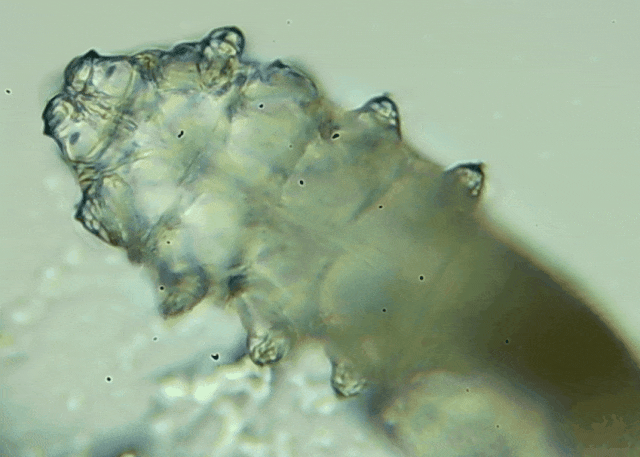

我只是眼睛癢,結(jié)果醫(yī)生說我睫毛里有80只蟲?這不是恐怖片,而是真實的病例:武漢一13歲男孩,右眼9根睫毛里檢出39只螨蟲,左眼9根里檢出47只。 而且這不是極端個案,廈門眼科中...

天哪,這么多螨蟲!王女士看著顯微鏡下的畫面,驚不住感嘆。 32歲的王女士近半年總感覺雙眼干澀、還經(jīng)常癢,早上醒來睫毛根部總有白色鱗屑,滴了不少人工淚液也沒緩解。前幾天...[詳細]

我只是眼睛癢,結(jié)果醫(yī)生說我睫毛里有80只蟲?這不是恐怖片,而是真實的病例:武漢一13歲男孩,右眼9根睫毛里檢出39只螨蟲,左眼9根里檢出47只。 而且這不是極端個案,廈門眼科中...[詳細]

瞼緣發(fā)炎可以涉及到瞼緣的任何一部分,包括睫毛、皮脂腺、瞼板腺以及瞼緣表面的這一系列結(jié)構(gòu)。 這種炎癥可以是非常急性的,比如說細菌急性感染;也可以是亞急性的,比如說螨蟲...[詳細]